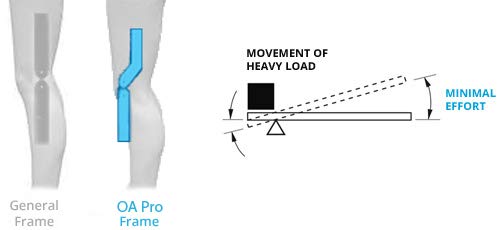

The posterior straps anchors on top of the calf and to the bottom of the hamstring. As the leg extends, the LTS Hinge gently pulls in the opposite directions, decompresses, and unloads the knee joint. This reduction of pressure supports and stabilizes the knee; eases pain and increases mobility. The LTS technology provides decompression to the knee joint by re-establishing the natural space and cushioning that’s missing between the femur and the tibia when afflicted with osteoarthritis.

Principle of Operation